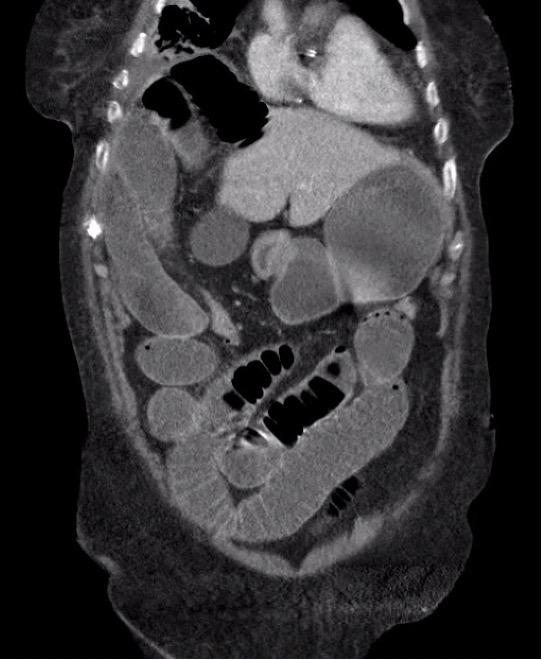

Radiologisch figuur van de romp.

Een 89-jarige vrouw komt op de SEH met sinds 2 dagen progressieve dyspneu na een periode van buikpijn en obstipatie. Bij auscultatie is verminderd ademgeruis rechts en crepiteren links basaal hoorbaar. De ademfrequentie is 48/min; de bloeddruk 68/32 mmHg. Er wordt een CT-scan van thorax en abdomen gemaakt.